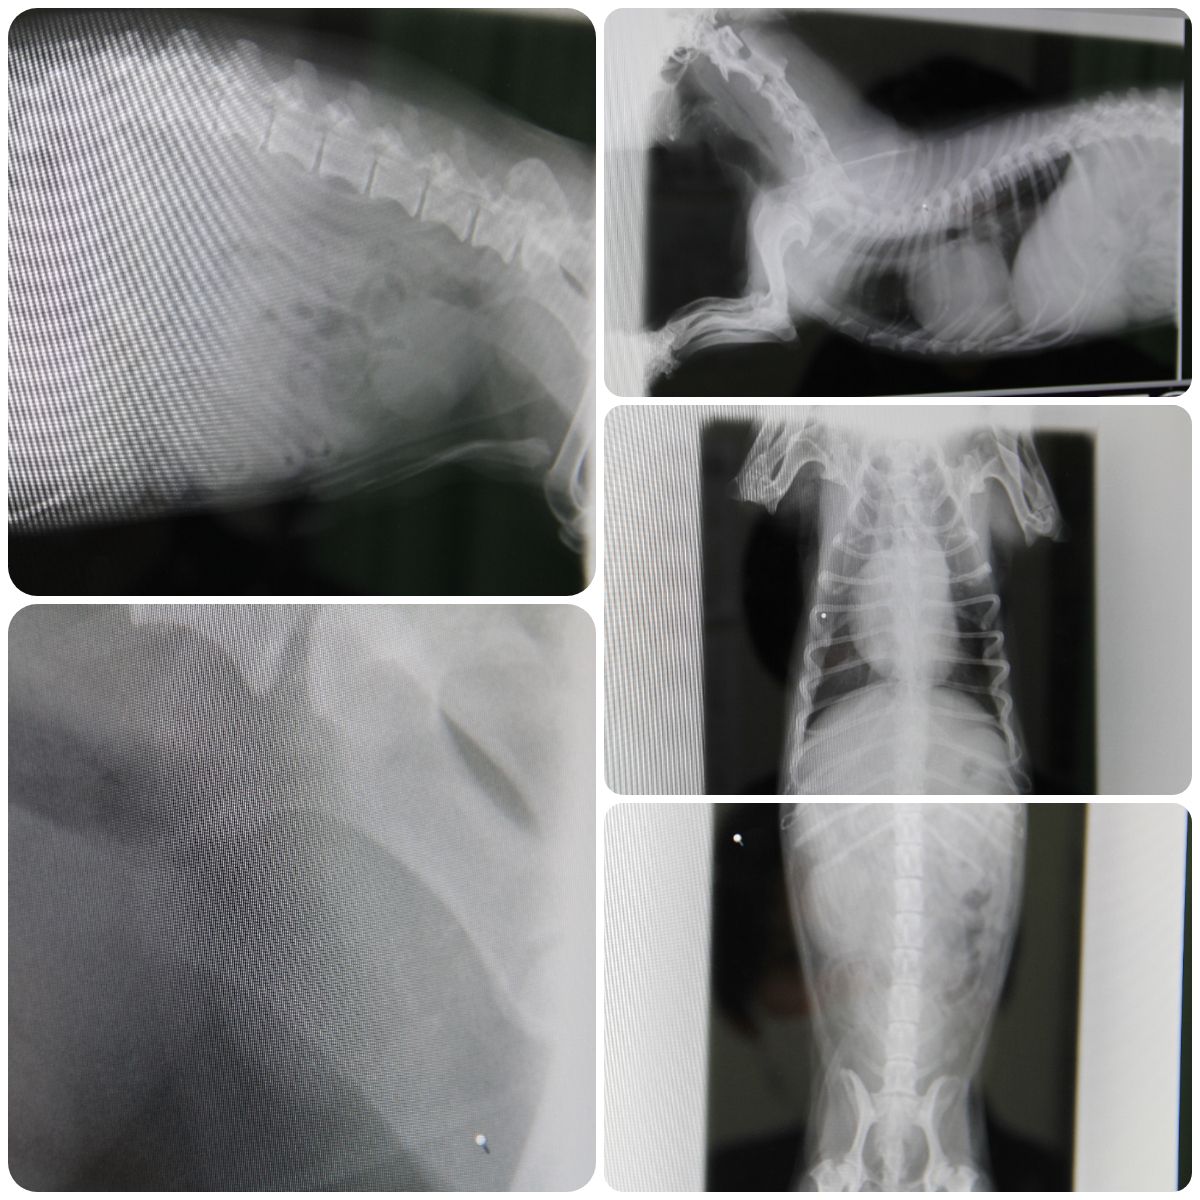

気になることがあって病院で診察だ ▼・。・▼… 2025年10月19日